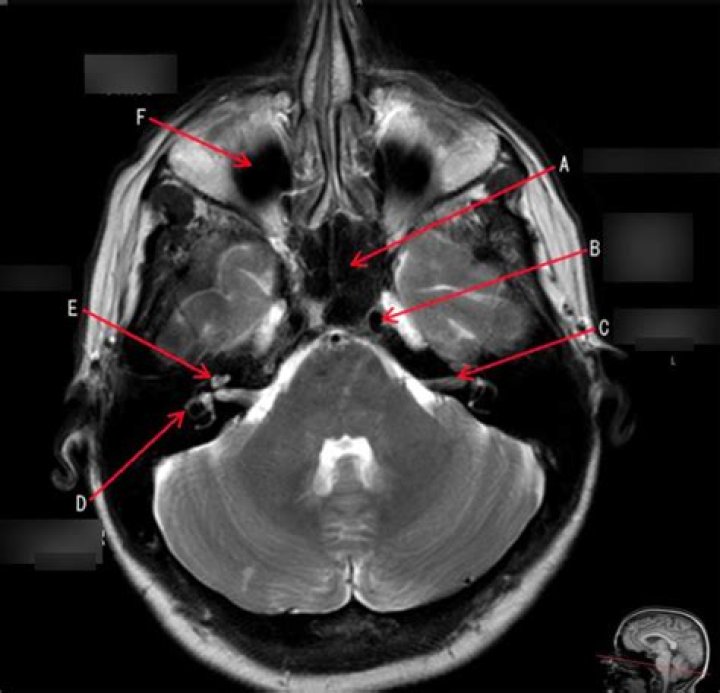

Magnetic resonance imaging (MRI) of the internal auditory canal (IAC) is a non-invasive, painless diagnostic imaging procedure that uses using radio waves and a strong magnetic field to create detailed images of the bony canal that transmits nerves and blood vessels from the base of the brain to the inner ear.

The internal acoustic canal (IAC), also known as the internal auditory canal or meatus (IAM), is a bony canal within the petrous portion of the temporal bone that transmits nerves and vessels from within the posterior cranial fossa to the auditory and vestibular apparatus.

Common applications of MRI include diagnostic evaluation of sensorineural hearing loss, assessment of cochlear implant candidacy, monitoring for residual or recurrent cholesteatoma within the tympanomastoid space, and monitoring for vestibular schwannoma within the inner auditory canal or cerebellopontine angle.

Magnetic resonance imaging (MRI) is presently the study of choice for assessment of the internal auditory canal (IAC). MRI provides excellent assessment of the IAC and the bony changes occurring in the canal walls, and it provides excellent demonstration of the content of the canal.